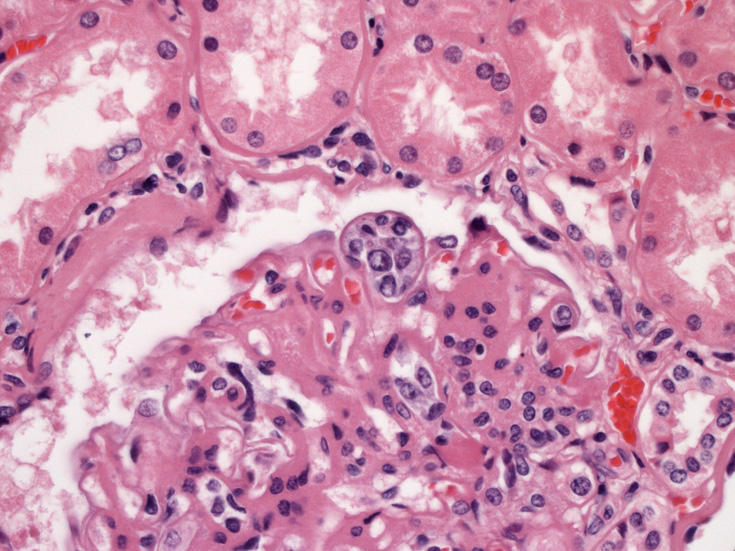

骨髄の組織所見

肺組織所見

血管内異常リンパ球増殖症例であるが、細胞はCD20陰性, CD79a陰性, CD3陰性である。BCR, TCR遺伝子再構成も認められなかった。(細胞量の関係もあるか?). EBER-ISHは周囲小型リンパ球に陽性所見を認めたが腫瘍細胞はEBER(-)であった。